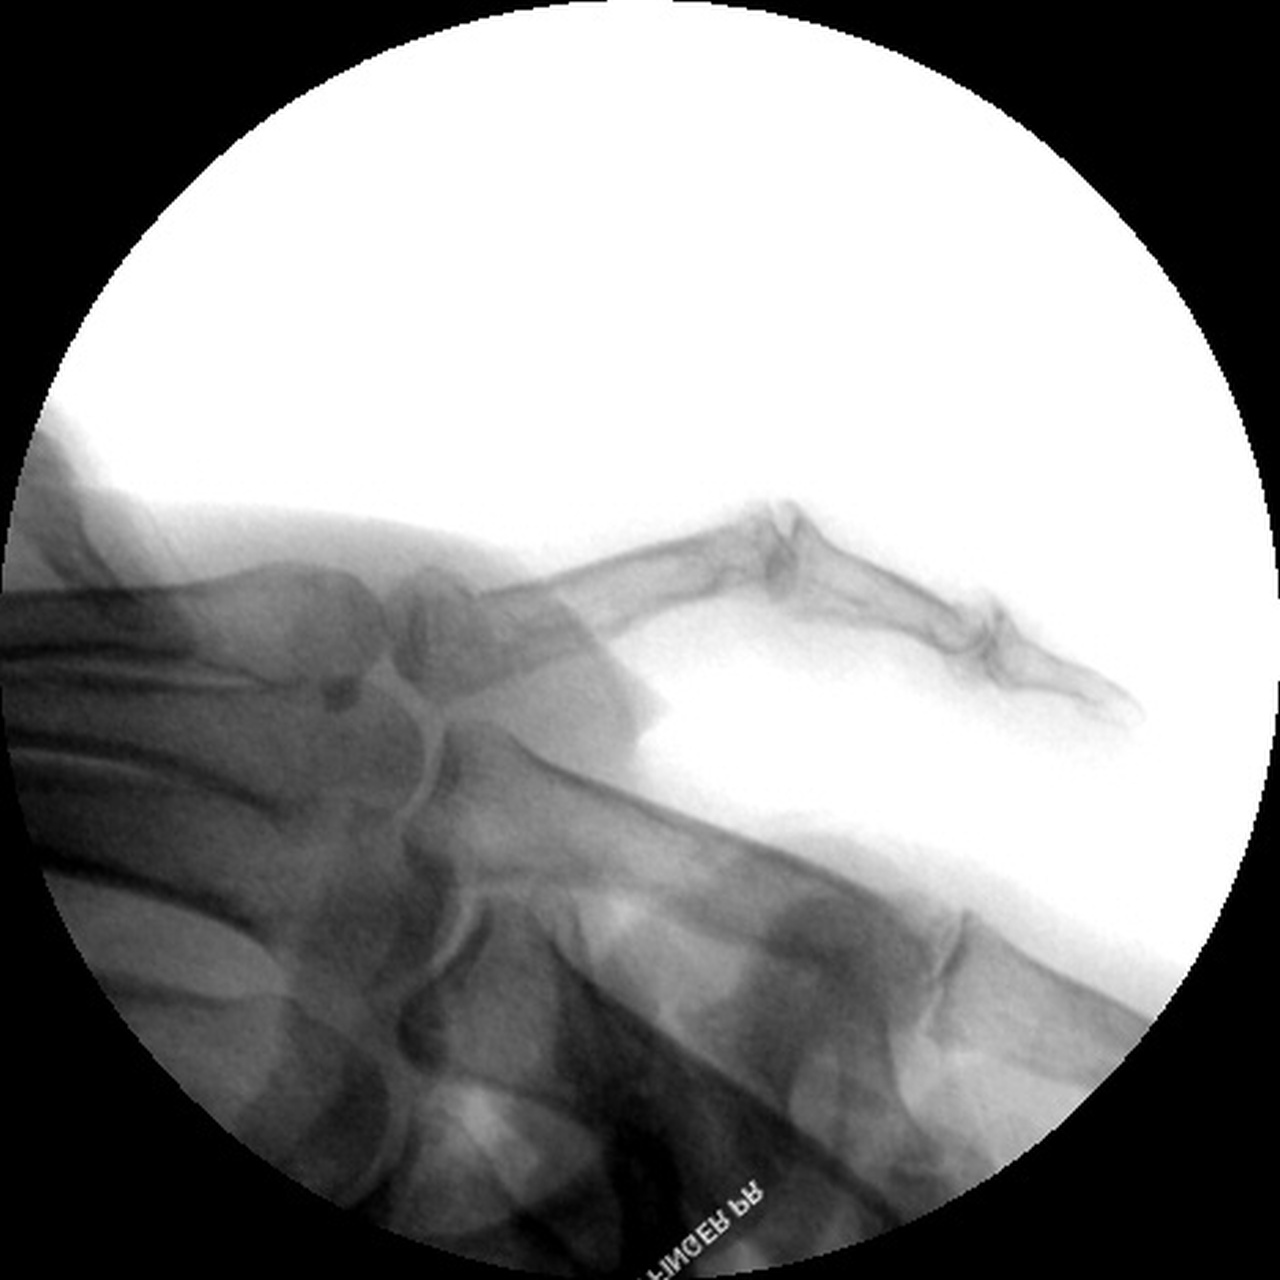

| With this

technique, the hand is immobilized in a protective

position splint for four weeks. Immediately before pin

removal. |

| Four weeks postop,

immediately prior to pin removal in the office. |